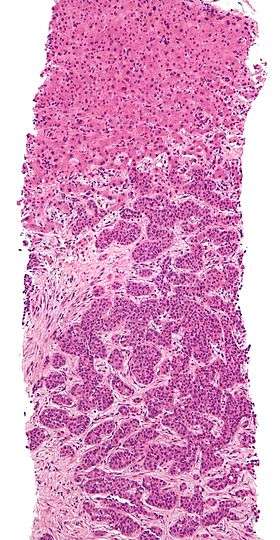

Metastasis proven by liver biopsy (tumor (adenocarcinoma) - lower two-thirds of image). H&E stain.

-